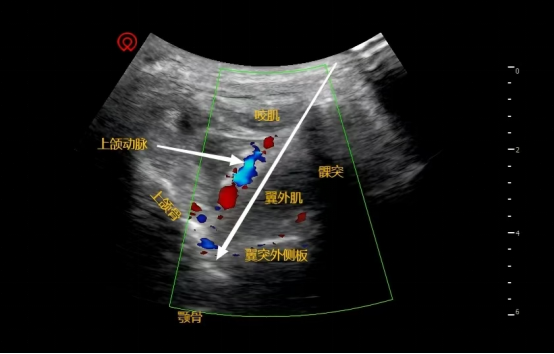

2如何治疗? 医生在超声引导下,将一根细针精准到达位于面部深部的蝶腭神经节附近,注入少量混合药物。能抑制神经异常活动,减轻黏膜炎症,快速缓解鼻塞、打喷嚏、流鼻涕等症状。

2如何治疗? 在超声实时可视下,将药物注射到颈部侧方的星状神经节周围。操作安全,精度高。